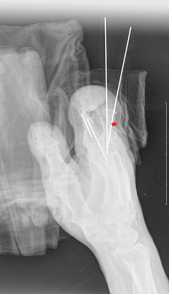

Культя рентген

Культя рентген 136 фотографий